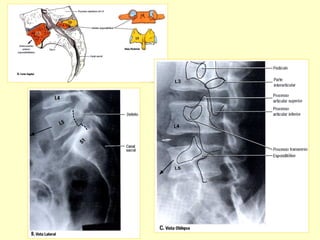

Incidências Básicas

Radiografias em A P e Perfil .

Para verificações dos forames intervertebrais

como também para avaliação dos arcos

posteriores , acrescentar incidências obliquas.

Para avaliações de eixo vertebral

acrescentar radiografias dinâmicas

em hiperextensão e hiperflexão.

Os pedículos

vertebrais são sede

preferenciais de

implantes metastáticos

METÁSTASE ÓSSEA

C – Vista Lateral